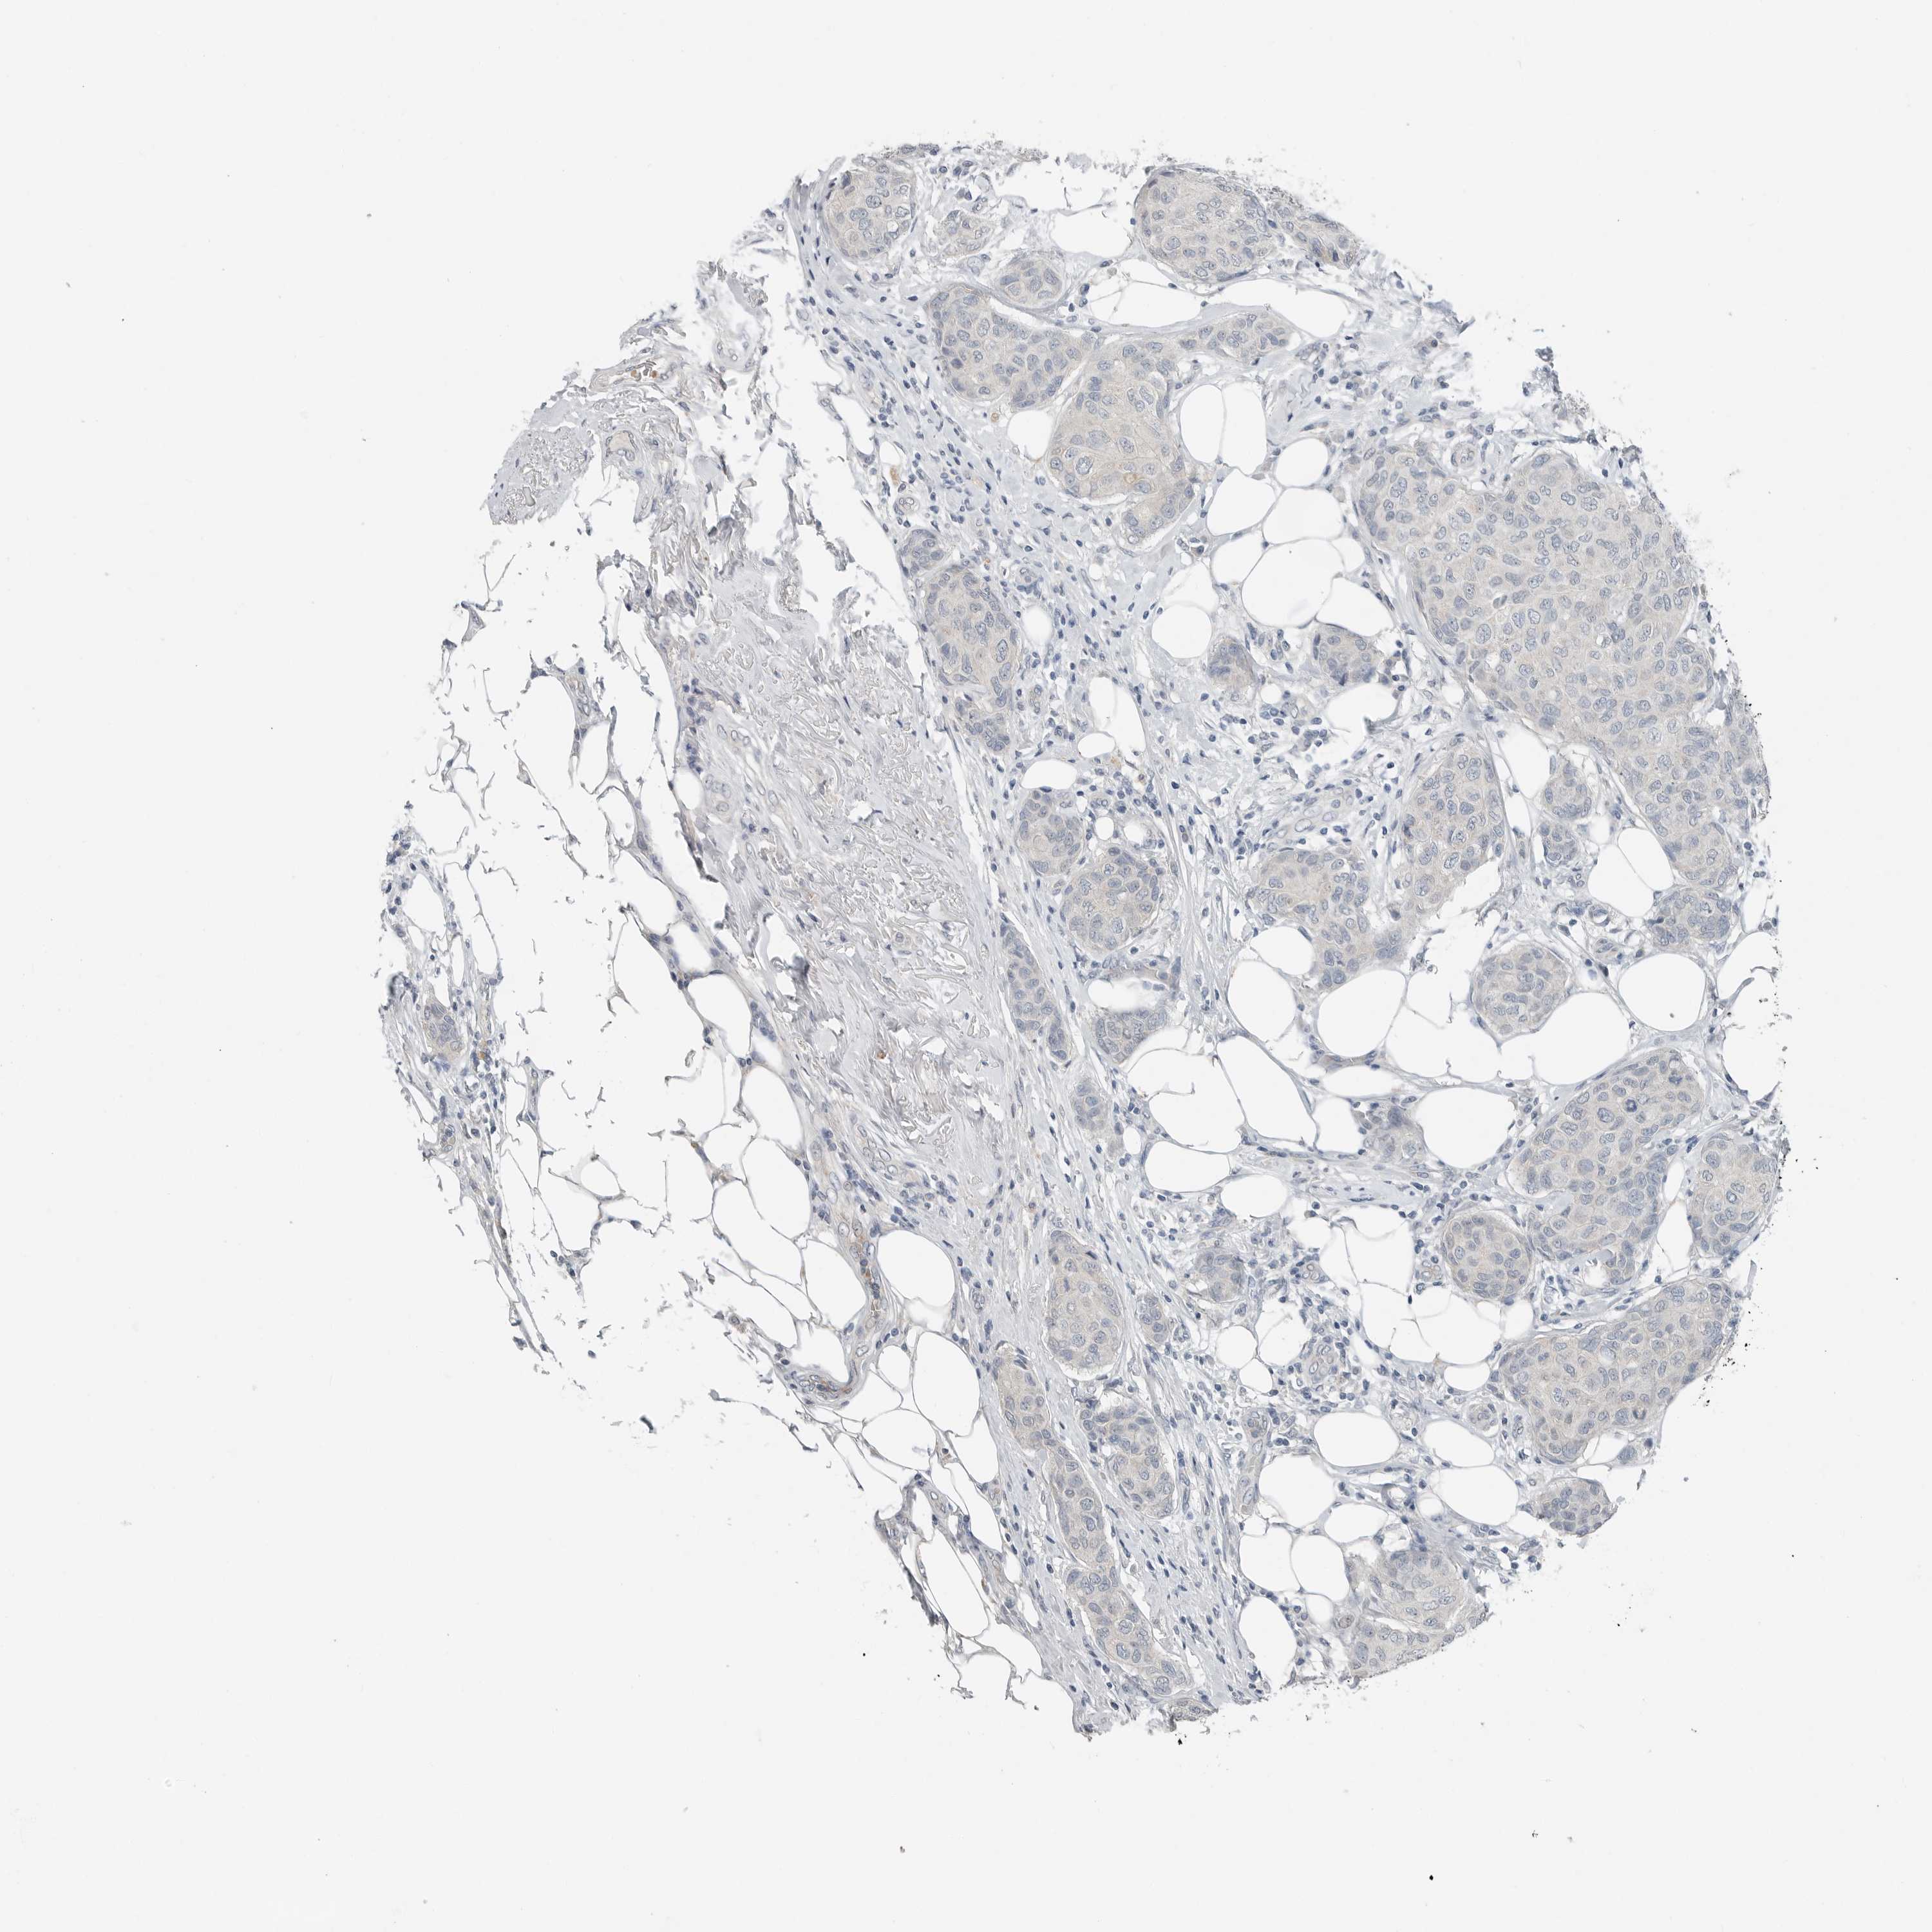

CANCER BREAST CANCER Show tissue menu

BRCA TCGA BRCA VALIDATION PROTEIN EXPRESSION

Breast cancer

Human cancer

Breast invasive carcinoma